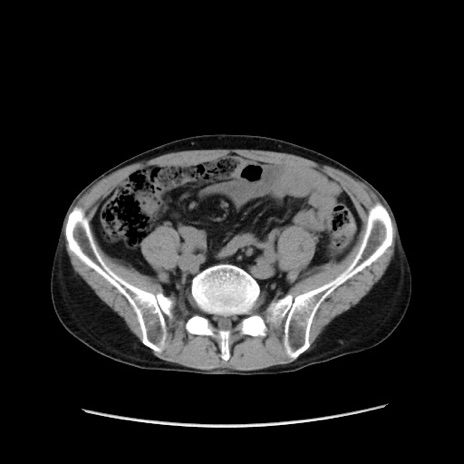

症例37(横断像)

【症例】40歳代 男性

【主訴】腹痛

【現病歴】4時間ほど前に電車に乗車中に臍部上より腹痛出現。徐々に増悪し起立困難となり、救急外来受診。生ものは数日食べていない。今朝お雑煮を食べた。

【身体所見】BT 36.8℃、BP 117/84mmHg、HR 91/min、SpO2 97%、苦悶様、腹部:臍上部広範囲圧痛あり、反跳痛±

【データ】WBC 8100、CRP 0.03